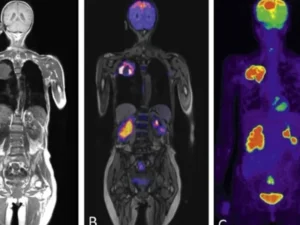

Tüm vücut MR, genellikle hastalıkların erken teşhisi ve yayılımının değerlendirilmesi amacıyla çekilir. Özellikle kanser taramaları, inflamatuar hastalıklar, enfeksiyonlar ve dejeneratif hastalıkların tespitinde kullanılır. Ayrıca, vücutta mevcut olan anormalliklerin detaylı bir şekilde incelenmesi için de tercih edilir.

Tüm vücut MR ile kanser türleri, tümörlerin yayılımı, inflamatuar hastalıklar, enfeksiyonlar, dejeneratif hastalıklar, sinir sistemi bozuklukları ve damar hastalıkları teşhis edilebilir. Bu yöntem, özellikle erken teşhis gerektiren hastalıklarda büyük önem taşır ve doktorların doğru tedavi yöntemini belirlemelerine yardımcı olur.